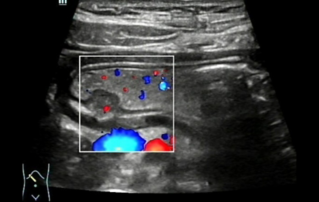

![a-hidden-world-uder-the-mucosa-case-report-of-ectopic-pancreas-in-stomach-wall-by-ultrasonography.thumb.319.319 Ultrasound Journal 5 - Hidden World Under the Mucosa - ??? ??? ?? Gastric Wall? Ectopic Pancreas ??]() Ultrasound Journal 5 - Hidden World Under the Mucosa - ??? ??? ?? Gastric Wall? Ectopic Pancreas ??Ectopic pancreas is a congenital anomaly. Contrast-enhanced ultrasound through the gastric window after oral administration of gastrointestinal contrast agent, reveals the clear anatomical structures and morphological characteristics of the lesions in all layers of the gastric wall.??? ?? | ??? ??? | ??? | ??? ???? | ?? 2022-11-15

Ultrasound Journal 5 - Hidden World Under the Mucosa - ??? ??? ?? Gastric Wall? Ectopic Pancreas ??Ectopic pancreas is a congenital anomaly. Contrast-enhanced ultrasound through the gastric window after oral administration of gastrointestinal contrast agent, reveals the clear anatomical structures and morphological characteristics of the lesions in all layers of the gastric wall.??? ?? | ??? ??? | ??? | ??? ???? | ?? 2022-11-15 -